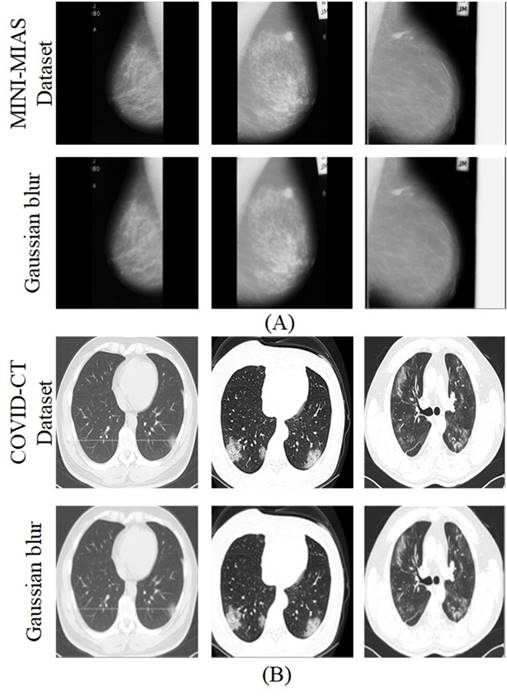

Initial processing is performed on the medical images with respect to grayscale conversions and Gaussian blur filtering, as shown in Figure 2.

The first two rows present the images from the MINI MIAS dataset of mammograms with the Gaussian blur filtering process respectively, while the last two rows present the images from the COVID-CT dataset of chest computed tomography with the Gaussian blur filtering. As mentioned, for the image format the mammograms did not require grayscale conversion, while for the CT scans grayscale conversion was applied before the Gaussian filtering process.